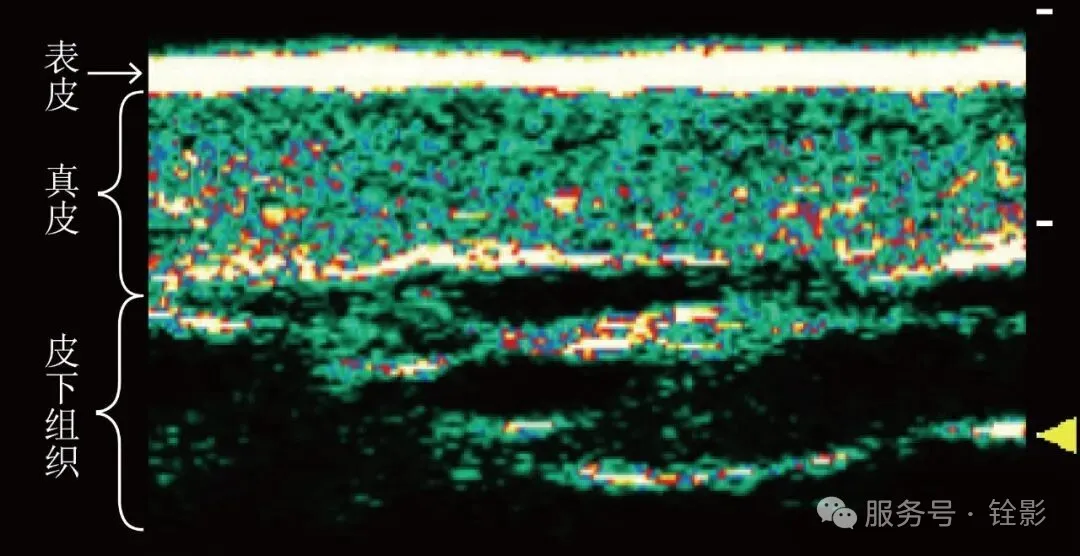

铨影皮肤超声凭借行业领先的20MHz高频探头,能呈现比常规超声更清晰的皮肤层次结构,真正做到术前可视化评估:

·个体皮肤结构可视化:高频探头可清晰显示肌底的层次结构和过往注射填充的情况。

·量化治疗方案:铨影超声搭载的智能分析系统可自动识别表皮、真皮、皮下脂肪等各层厚度和密度,为个性化填充剂量与能量设备参数提供客观数据支持。